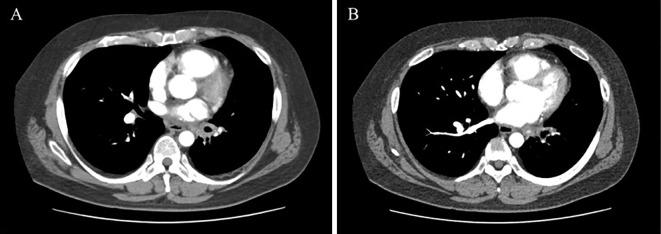

We herein report a 48-year-old man with a history of chronic atrial fibrillation (AF) and repeated hemoptysis after radiofrequency ablation. Contrast tomography showed soft tissue thickening of the left hilar region and left pulmonary vein stenosis. We performed bronchial artery embolization, but the hemoptysis did not disappear, and AF was not controlled. We performed left lung lobectomy and maze procedures since we considered surgical removal necessary as radical treatment. After the surgery, hemoptysis and atrial fibrillation did not recur. Refractory hemoptysis after catheter ablation is rare, but occasionally occurs in patients with severe pulmonary vein stenosis.

我们在此报告一例 48 岁男性,患有慢性心房颤动(AF)病史,射频消融术后反复咯血。对比断层扫描显示左肺门区软组织增厚,左肺静脉狭窄。我们进行了支气管动脉栓塞,但咯血并未消失,AF 也未得到控制。我们考虑到作为根治性治疗有必要进行手术切除,因此进行了左肺叶切除术和迷宫手术。手术后,咯血和心房颤动均未再复发。射频消融术后难治性咯血较为罕见,但在严重肺静脉狭窄患者中偶有发生。